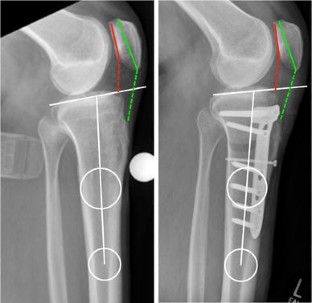

Fig. 3